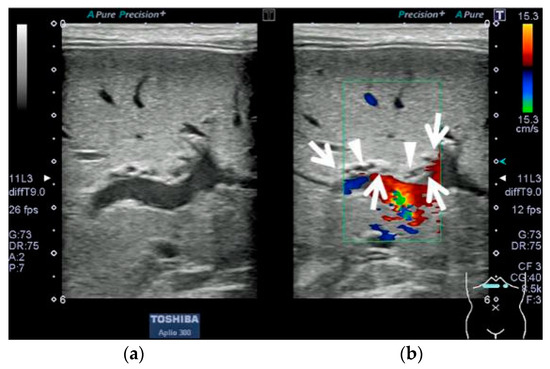

2.1. Case 1: 4-Day-Old Boy